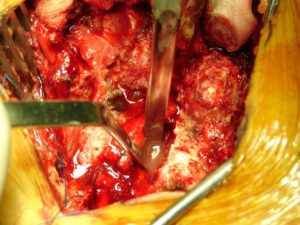

Στην πρώτη φάση, κατόπιν οπισθίας ανοικτής εκτεταμένης προσπέλασης, έγινε ευρεία πεταλεκτομή του 3ου και 4ου οσφυϊκού σπονδύλου και παροχέτευση του αποστήματος. Δόθηκε υλικό από τους ιστούς και του πύου για καλλιέργειες.

Εικόνα 4 (α,β)

- α

- β